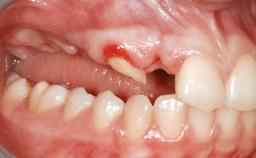

A 47-year-old woman who had suffered from aggressive periodontitis requiring a number of periodontal interventions over more than 10 years was referred by her general dental practitioner and periodontologist for bone augmentation and implant therapy. Her failing dentition had already been scheduled for extraction. The patient expressed a desire for implant-supported fixed restorations and esthetic improvement of her lower face. She had agreed to consult with a maxillofacial surgeon after the referring dentist had suggested bone augmentation. An initial examination by the maxillofacial surgeon revealed mobility of all residual teeth in a patient who was very unhappy with the function of her removable partial dentures. Due to periodontally migrated flaring teeth and loss of occlusal support, the vertical dimension of occlusion was dramatically reduced. The patient was displeased with her lower face because of deepened nasolabial, commissural, and supramental folds.

Bone Augmentation Horizontal|Sinus Floor Elevation|Staged|Vertical